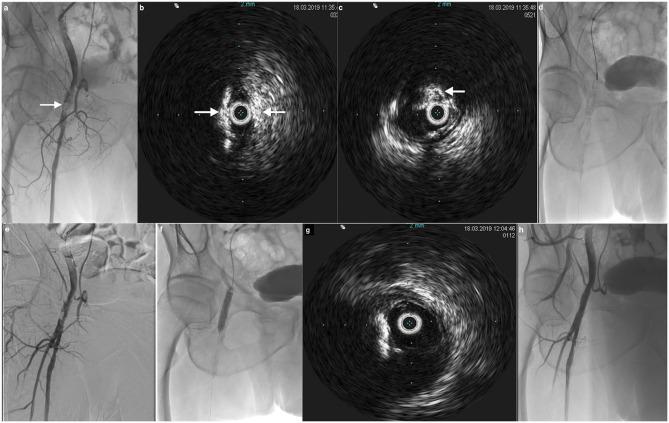

Over the last decade, intravascular ultrasound (IVUS) has emerged as a useful adjunctive tool to angiography in an increasing number of catheter-based procedures for peripheral arterial disease (PAD). IVUS catheters offer accurate cross-sectional imaging of arterial vessels with high dimensional accuracy and provide accurate information about lesion morphology. IVUS enables assessment of the plaque morphology, vessel diameter, and the presence of arterial dissections. Furthermore, IVUS is able to properly guide the best choice of appropriate percutaneous transluminal angioplasty (PTA) technique, guide the delivery of different devices, and assess the immediate result of any endovascular intervention. In the present review, the role of IVUS for PAD will be discussed, specifically the applications of IVUS technology during interventional procedures including PTA, stent sizing, crossing total occlusion, assessing residual narrowing and stent apposition and expansion, and atherectomy. Future perspectives of IVUS-guided treatments and cost-effectiveness of the systematic use of IVUS during endovascular interventions will be also discussed.

在过去十年中,血管内超声(IVUS)在越来越多的用于治疗外周动脉疾病(PAD)的导管介入手术中,已成为血管造影的一种有用辅助工具。IVUS导管能够对动脉血管进行精确的横断面成像,具有很高的尺寸精度,并能提供有关病变形态的准确信息。IVUS可用于评估斑块形态、血管直径以及动脉夹层的存在情况。此外,IVUS能够恰当地指导选择最合适的经皮腔内血管成形术(PTA)技术,引导不同器械的输送,并评估任何血管内介入治疗的即时效果。在本综述中,将讨论IVUS在PAD治疗中的作用,特别是IVUS技术在包括PTA、支架尺寸选择、穿越完全闭塞病变、评估残余狭窄以及支架贴壁和扩张情况,以及旋切术等介入手术中的应用。还将讨论IVUS引导治疗的未来前景以及在血管内介入治疗中系统使用IVUS的成本效益。